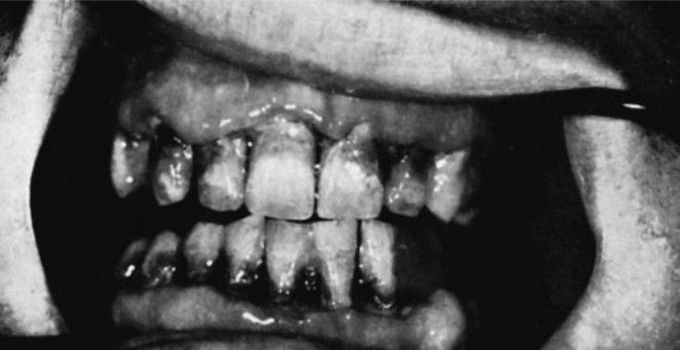

Acute necrotizing ulcerative gingivitis

Extensive necrosis of the interdental papillae, and marginal and attached gingivae caused by acute necrotizing ulcerative gingivitis